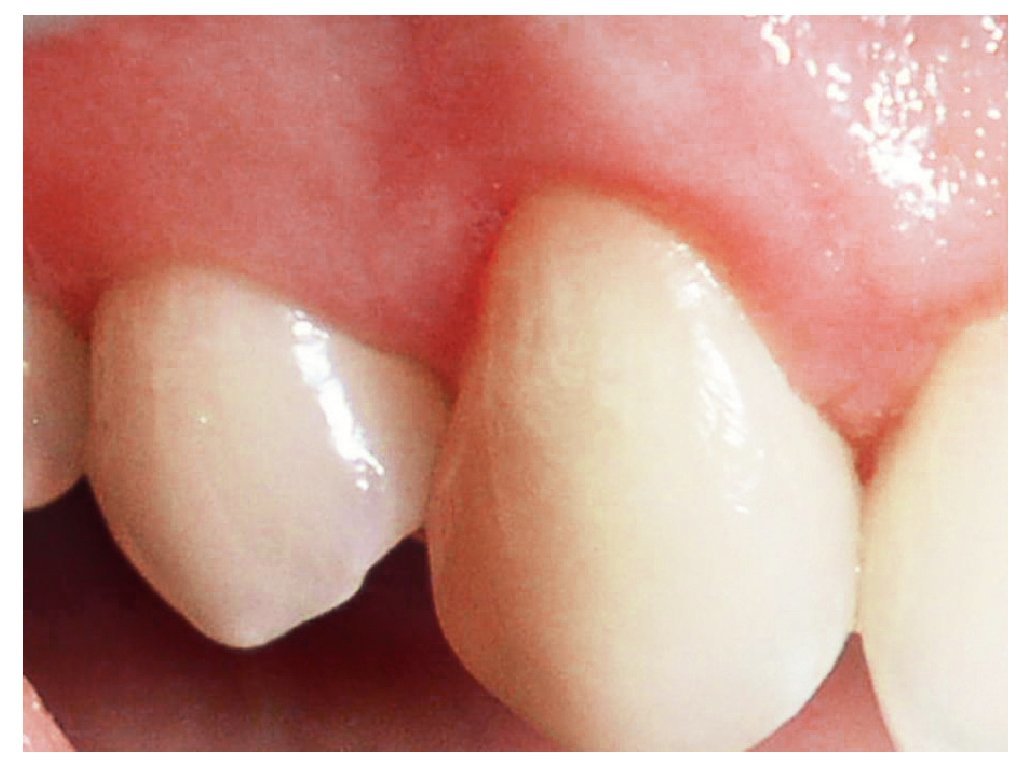

En el curso de la curación, el margen de tejidos blandos sobre los dientes tratados mostró cierto grado de contracción en los primeros meses (fig. 9). En el control de 1 año, se observó una cobertura radicular completa en ambos casos (100% de cobertura radicular) (figs. 8 y 10) con profundidades de sondaje de 0,5 mm y una ganancia de inserción clínica de 5,0 mm en cada caso, indicando una reducción de 0,5 mm en la profundidad de sondaje y un tejido de cobertura de 0,5 mm de altura (encía por encima de la UAC). En ambos casos aumentó la cantidad de encía queratinizada, revelando una ganancia de 4,0 mm y 6,5 mm respectivamente. En los dientes donantes no se produjo ninguna recesión.

Figura 10. Aspecto clínico postoperatorio a los doce meses del caso 2.